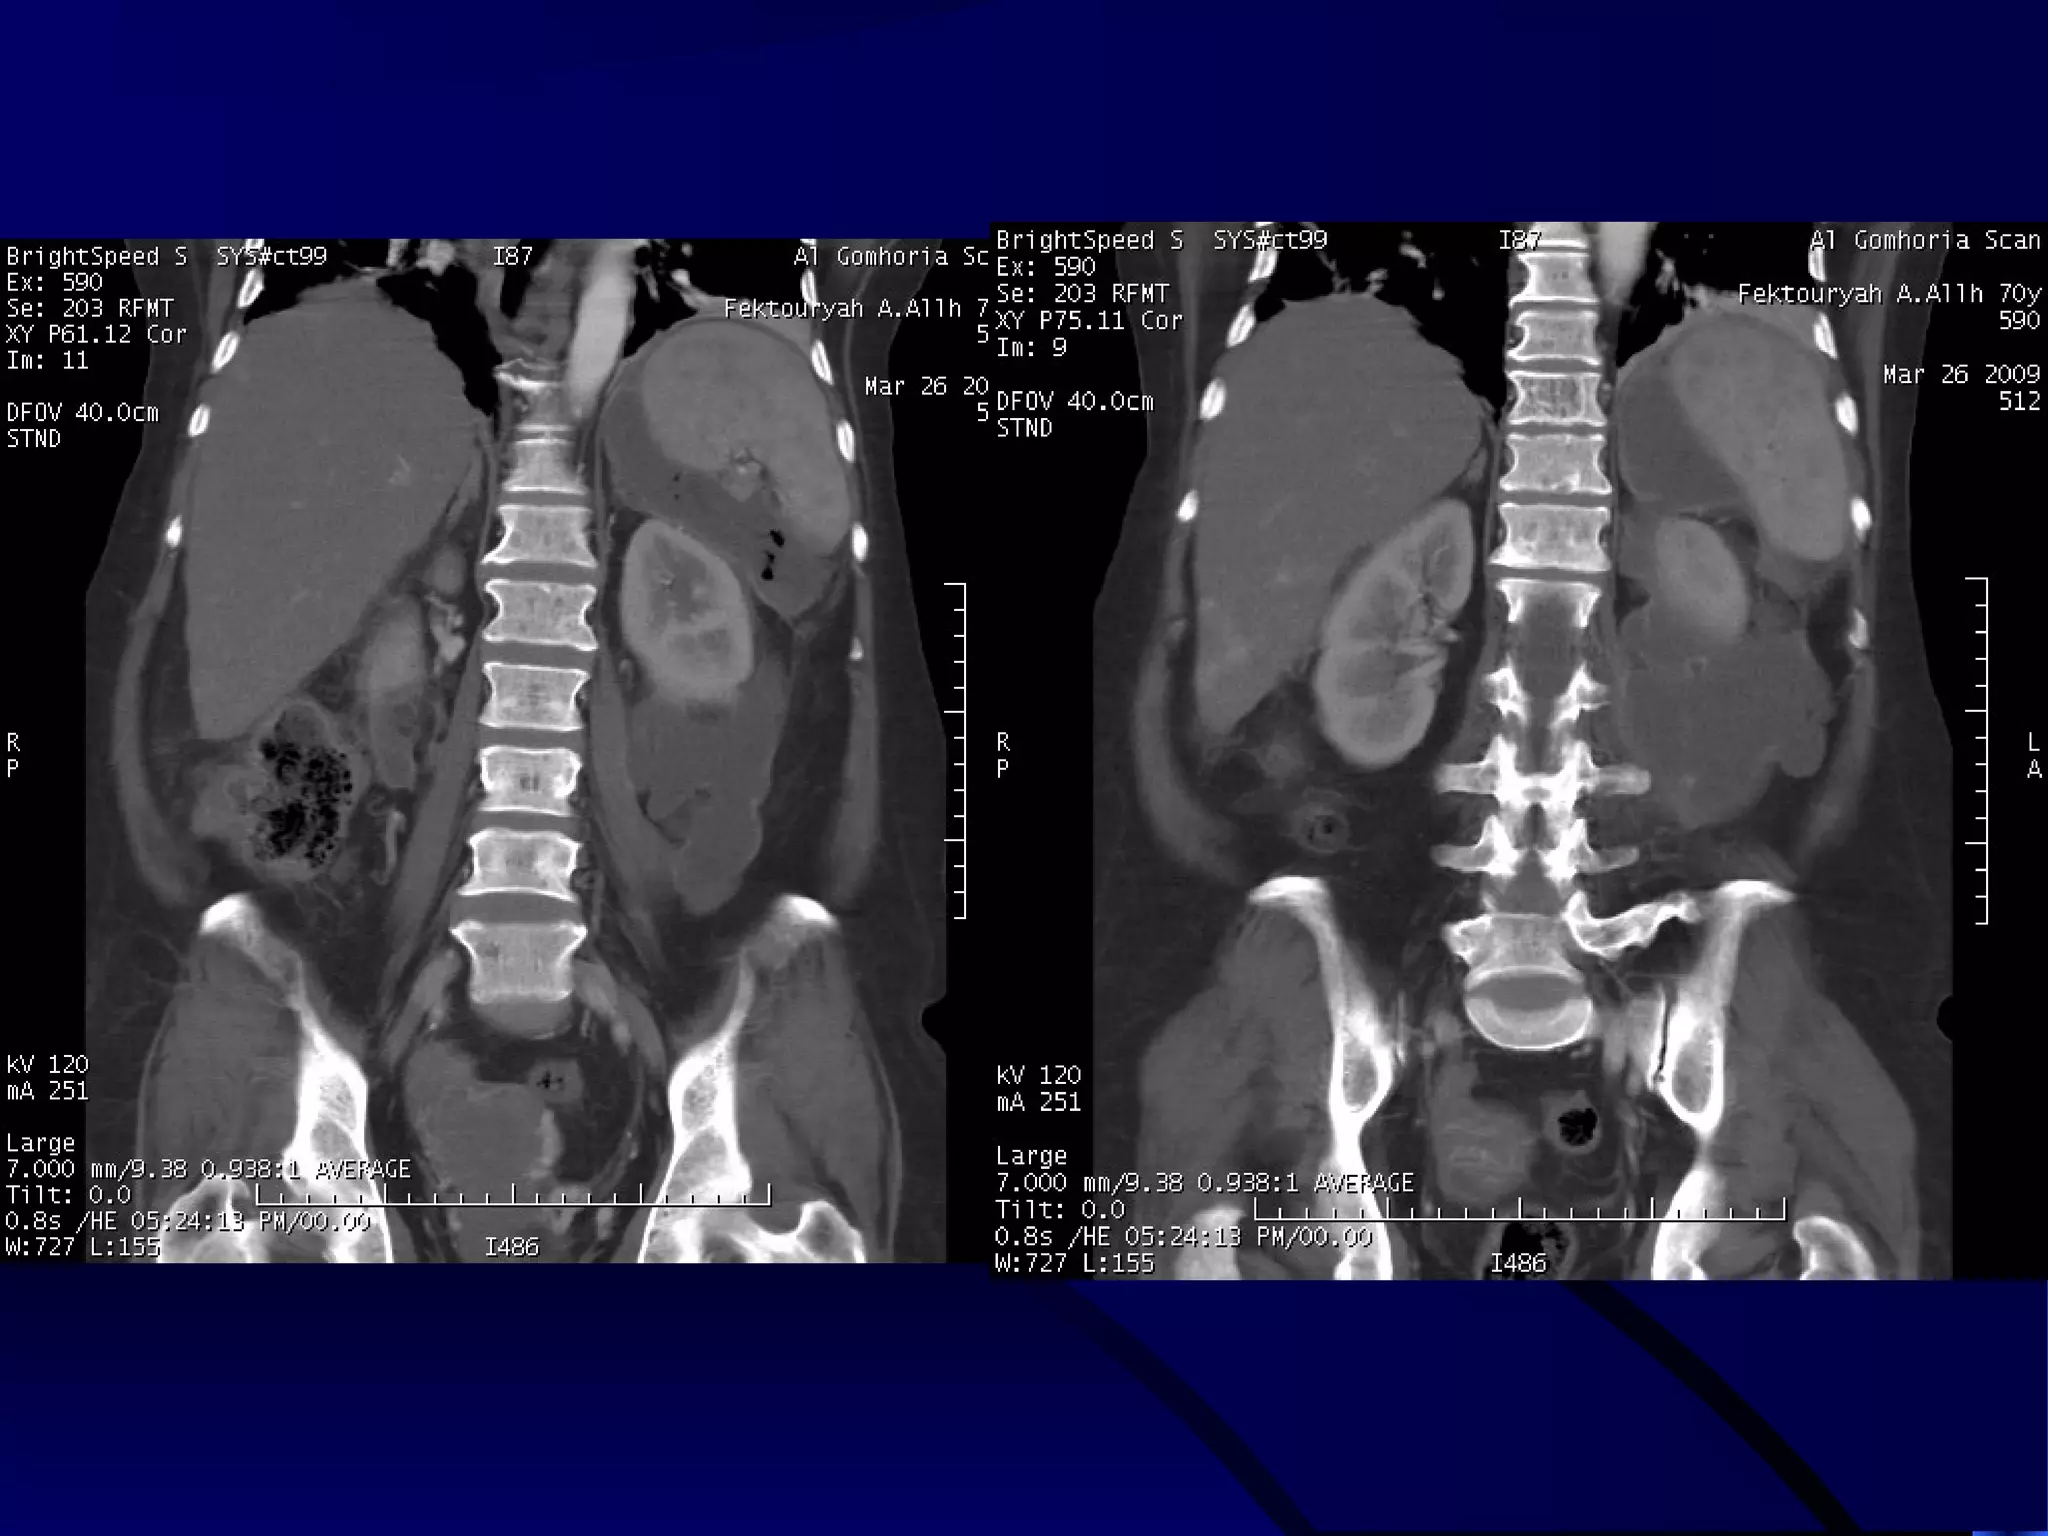

CASE (2)

OBSTRUCTED INFECTED KIDNEY

ENLARGED LEFT KIDNEY WITH MARKED STRANDING OF THE

PERINEPHRIC FAT AND OBSTRUCTING PELVIC CALCULUS

DOUBLE DENSITY VR IMAGE SHOWING

THE OBSTRUCTING CALCULUS